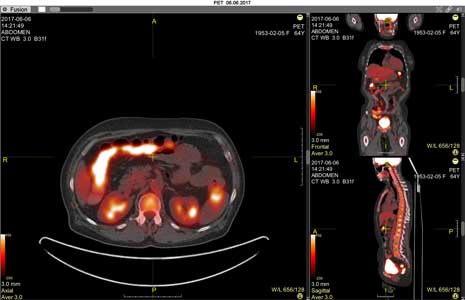

Fusion mode is designed to superimpose two volumes on top of each other

Applicable only for CT, MRI, and PET studies

Click the OK button to switch to "Fusion" mode: